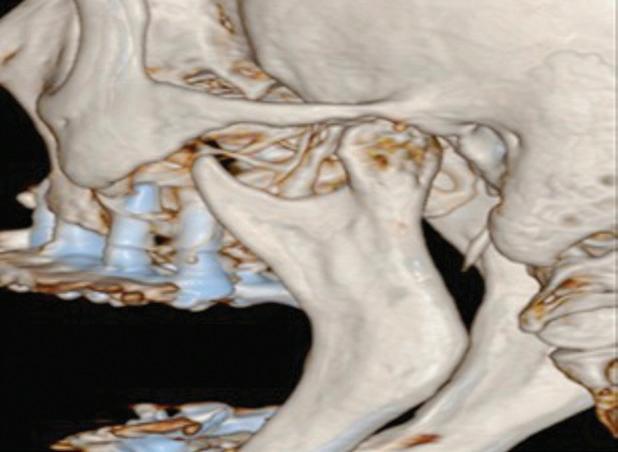

Paciente do sexo feminino, 62 anos de idade, com diagnóstico de doença degenerativa das duas articulações temporomandibulares, classificação de Wilkes V. A paciente possuía próteses do tipo protocolo superior e inferior. Relatava um quadro de dor intensa bilateral das articulações temporomandibulares. Havia limitação de abertura bucal e alteração de oclusão. Na tomografia computadorizada, o côndilo apresentava reabsorção e erosão da superfície óssea (Fig. 1). O plano de tratamento proposto foi a condilectomia e reconstrução aloplástica de ambas as articulações temporomandibulares.

Figura 1: A) Vista frontal da paciente em repouso. B) Vista lateral da paciente em repouso. C) Próteses protocolo superior e inferior. D) Abertura bucal máxima reduzida, de 27 mm. E) Vista lateral direita em tomografia computadorizada, apresentando reabsorção do côndilo da mandíbula. F) Vista lateral esquerda em tomografia computadorizada, apresentando reabsorção do côndilo da mandíbula.